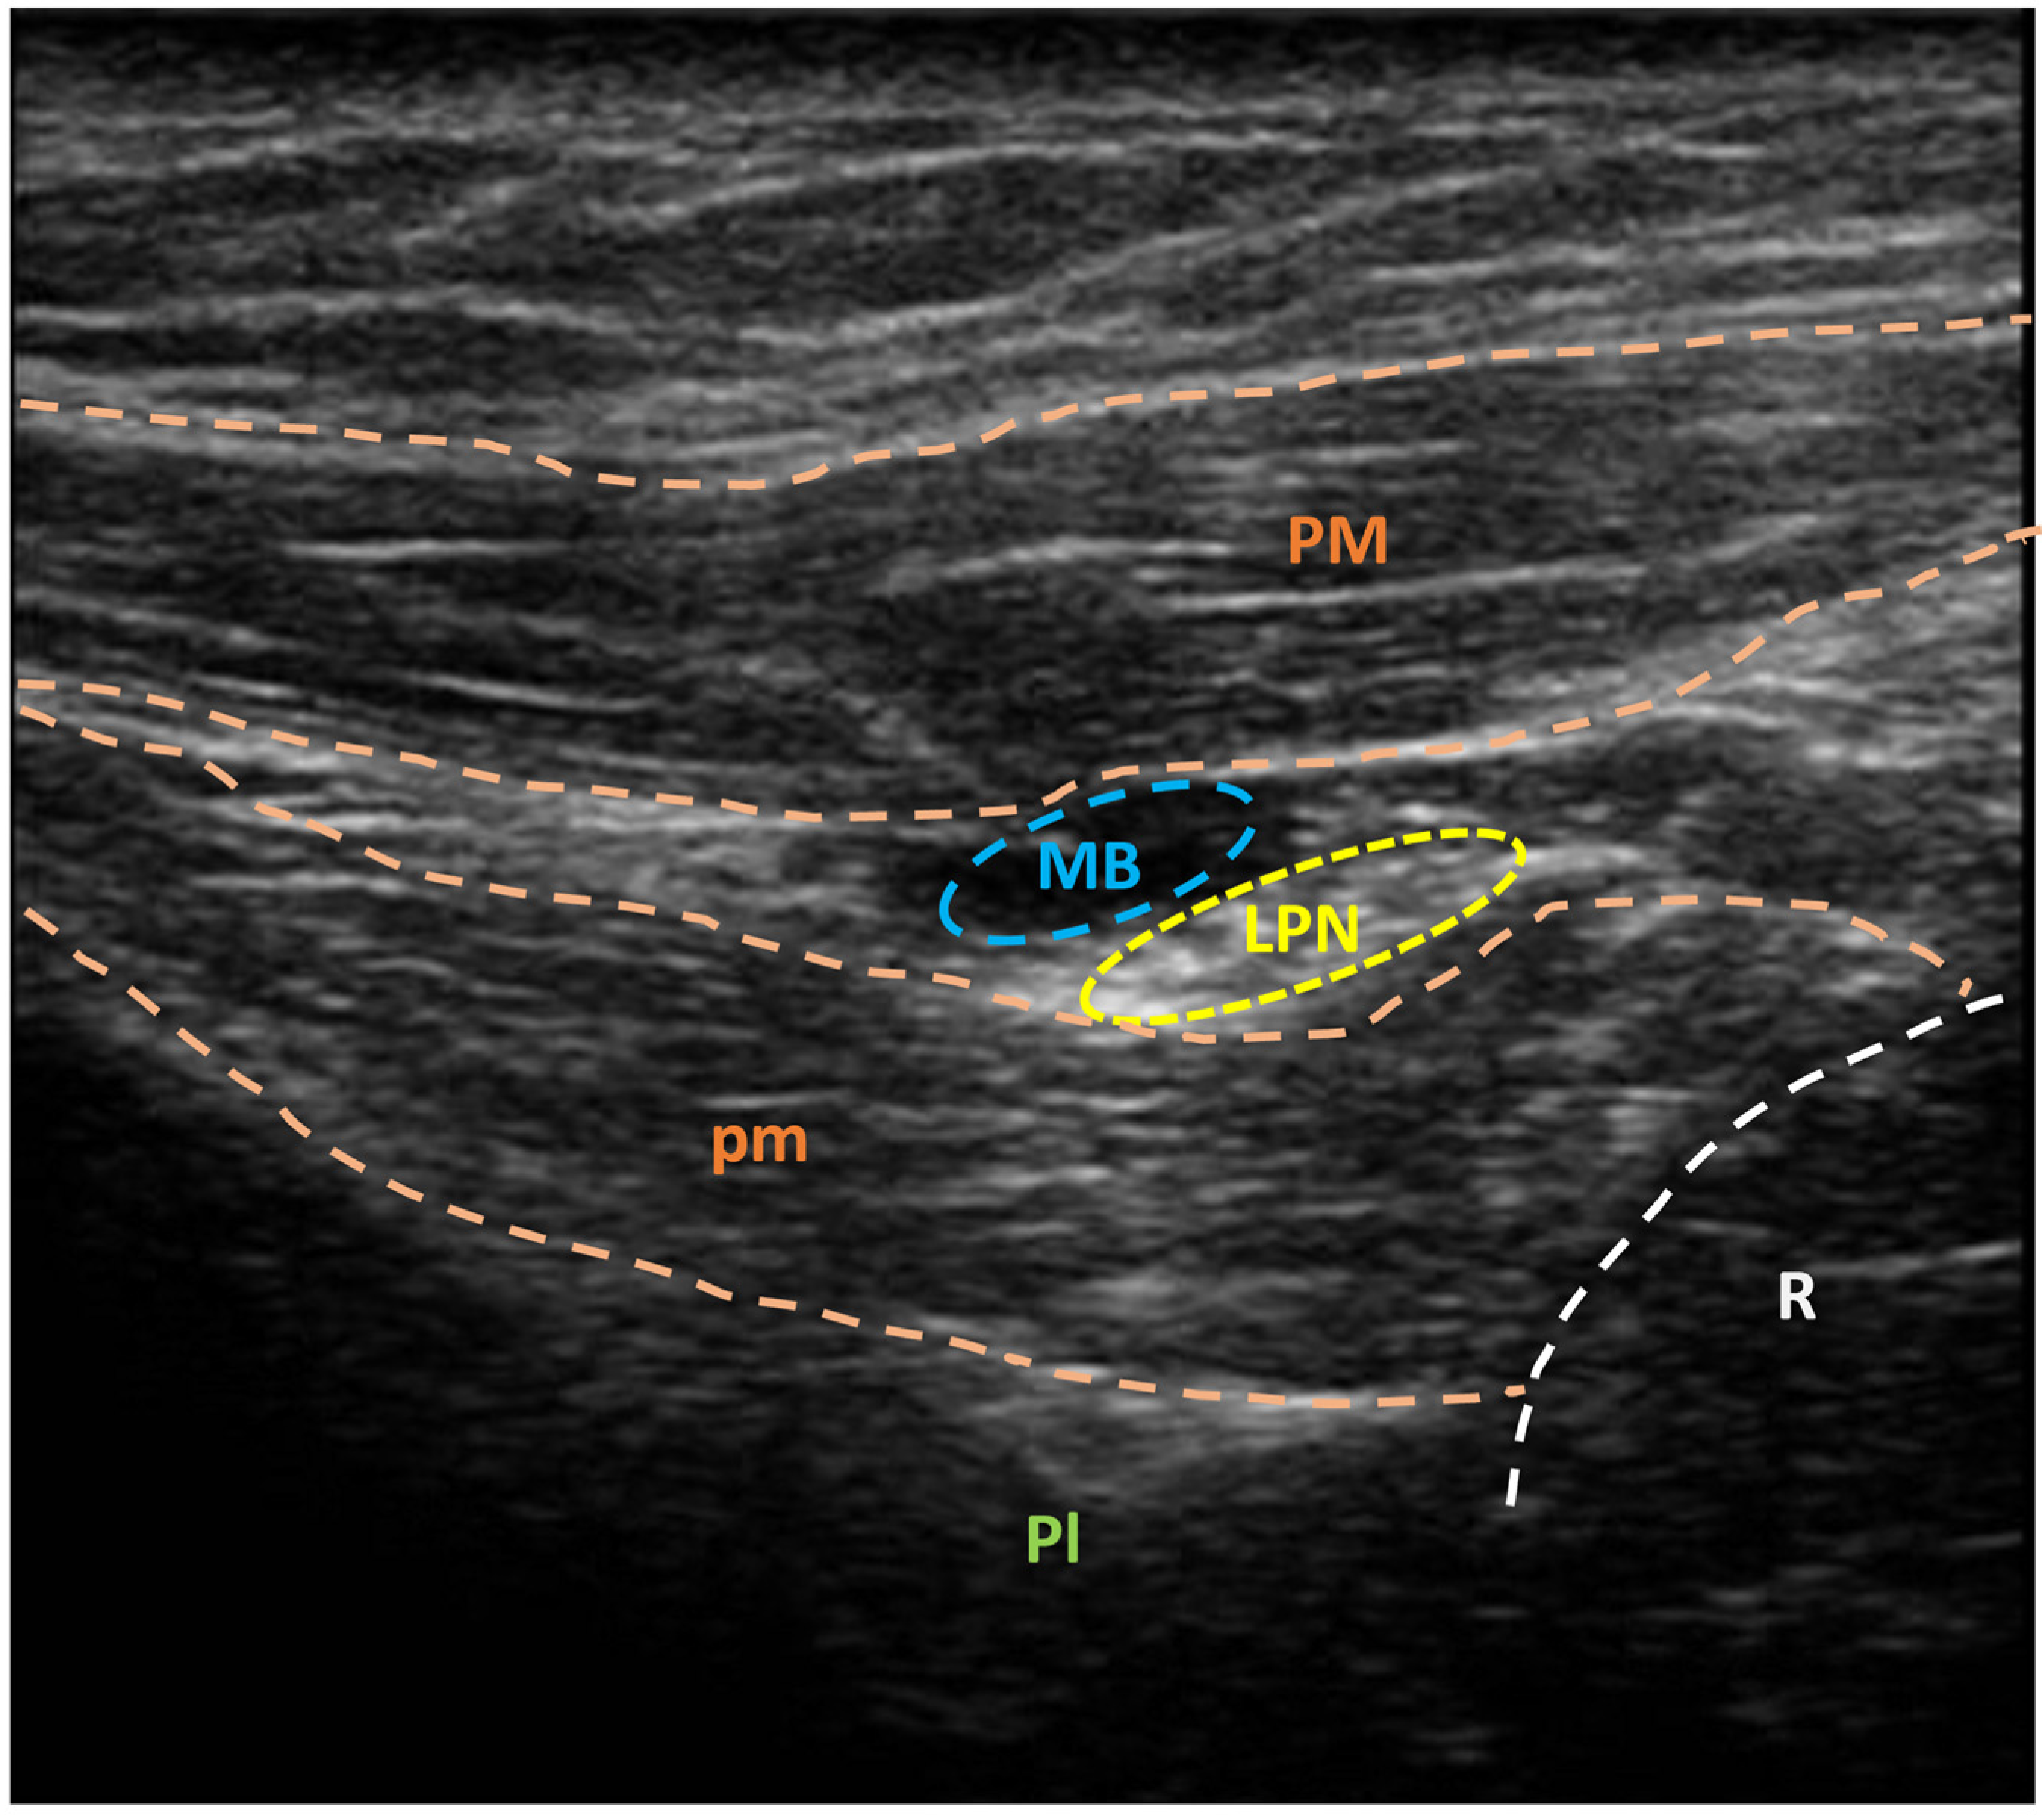

3.2. US-Guided Nerve Localization and Marking